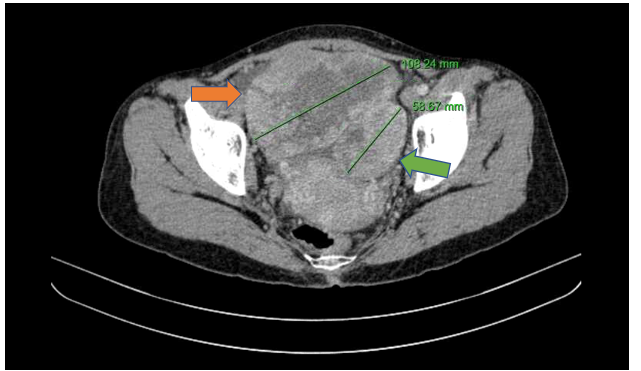

Hình 5. Hình ảnh khối buồng trứng phải kích thước ~108mm (mũi tên màu cam), khối buồng trứng trái kích thước ~58mm (mũi tên màu xanh lục)trên phim chụp cắt lớp vi tính.